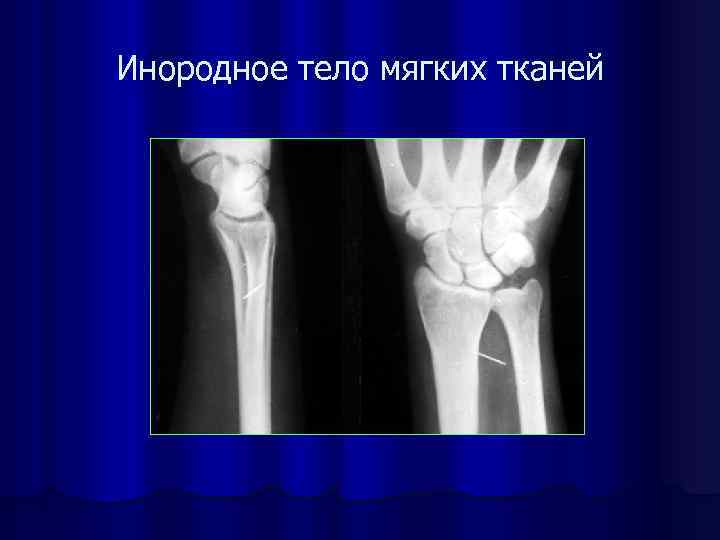

Инородное тело мягких тканей